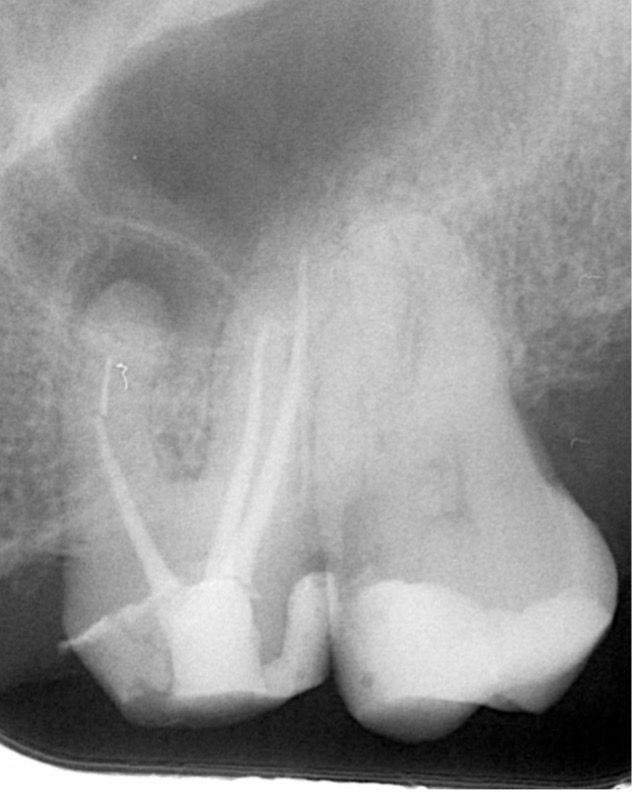

Yaklaşık 9 ay sonra hasta yapılan kontrolde (2024 Şubat) meziobukkal kök ucunda subklinik şekilde seyreden lezyon olduğu görüldü. Ancak hasta mevcut durumda tekrar tedaviyi kabul etmedi (Şekil 3). (Reddetti)

(Şekil 3). 2024 Şubat kontrol meziobukkal kök ucunda periapikal lezyon